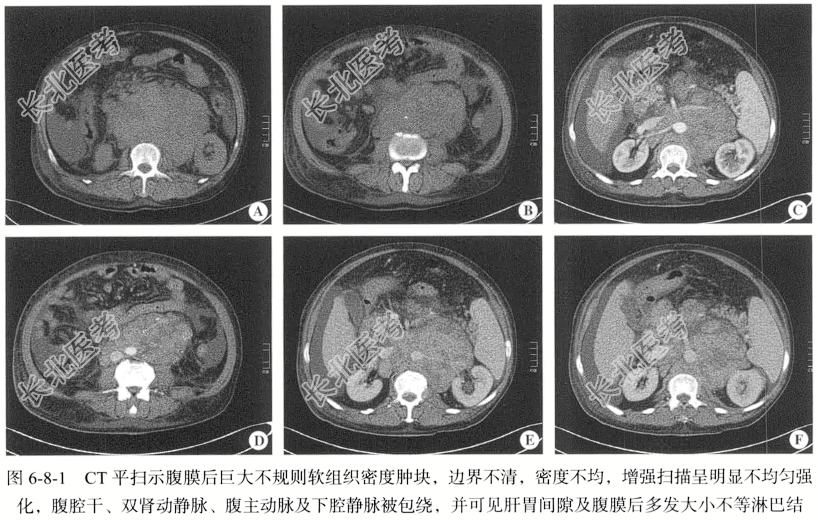

【影像图片】见图6-8-1。

【手术所见】腹膜后见一大小约9.8cm×7.2cm的肿块,肿块伴出血,邻近腹膜呈灰暗色,已被侵犯。